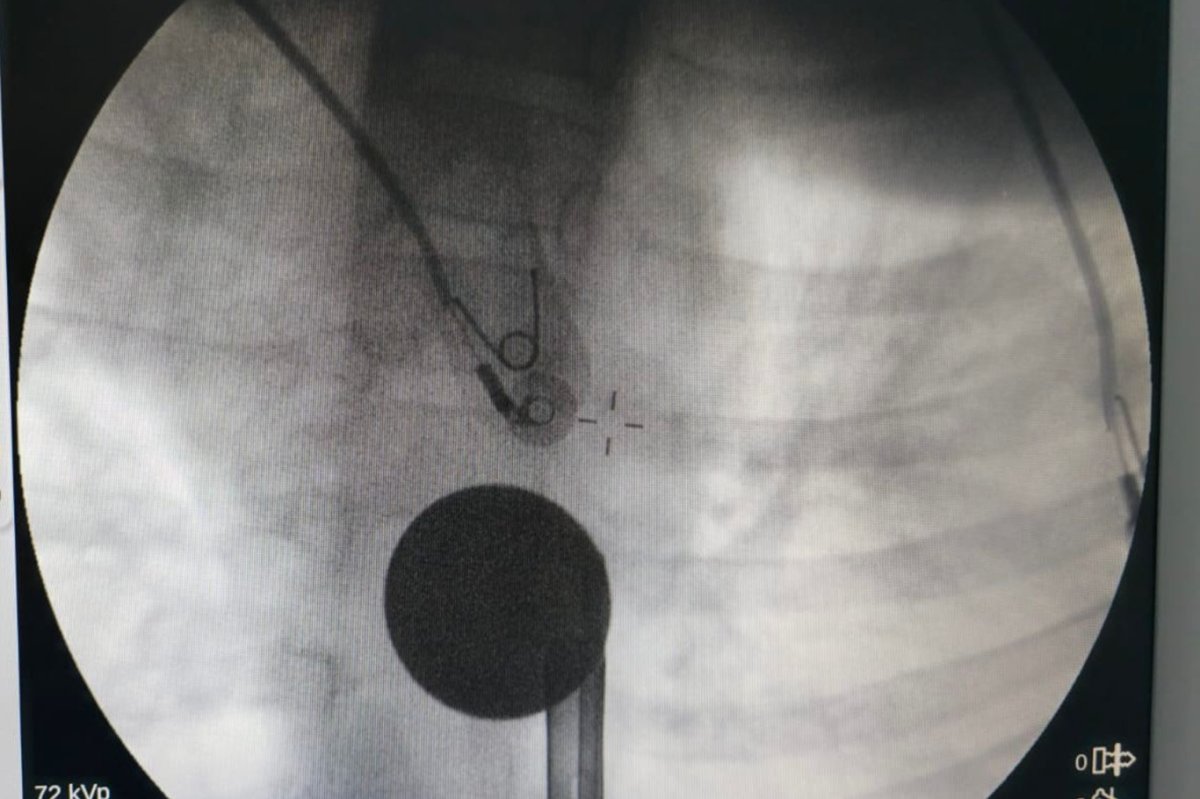

Yapılan incelemelerde 5 TL’lik madeni paranın Y.K.’nin yemek borusuna kadar ilerlediği belirlendi. Çocuk hastalarda ciddi solunum ve sindirim sistemi riskleri oluşturabilen bu durum üzerine ilgili branşlar vakit kaybetmeden harekete geçti.

Madeni paranın çıkarılması için Gastroenteroloji Uzmanı Dr. Yaren Dirik ile Kulak Burun Boğaz (KBB) Hekimi Dr. Yasin Gökçınar tarafından ortak bir girişim gerçekleştirildi. Alanında uzman ekiplerin koordineli çalışmasıyla madeni para herhangi bir komplikasyona yol açmadan başarıyla çıkarıldı.